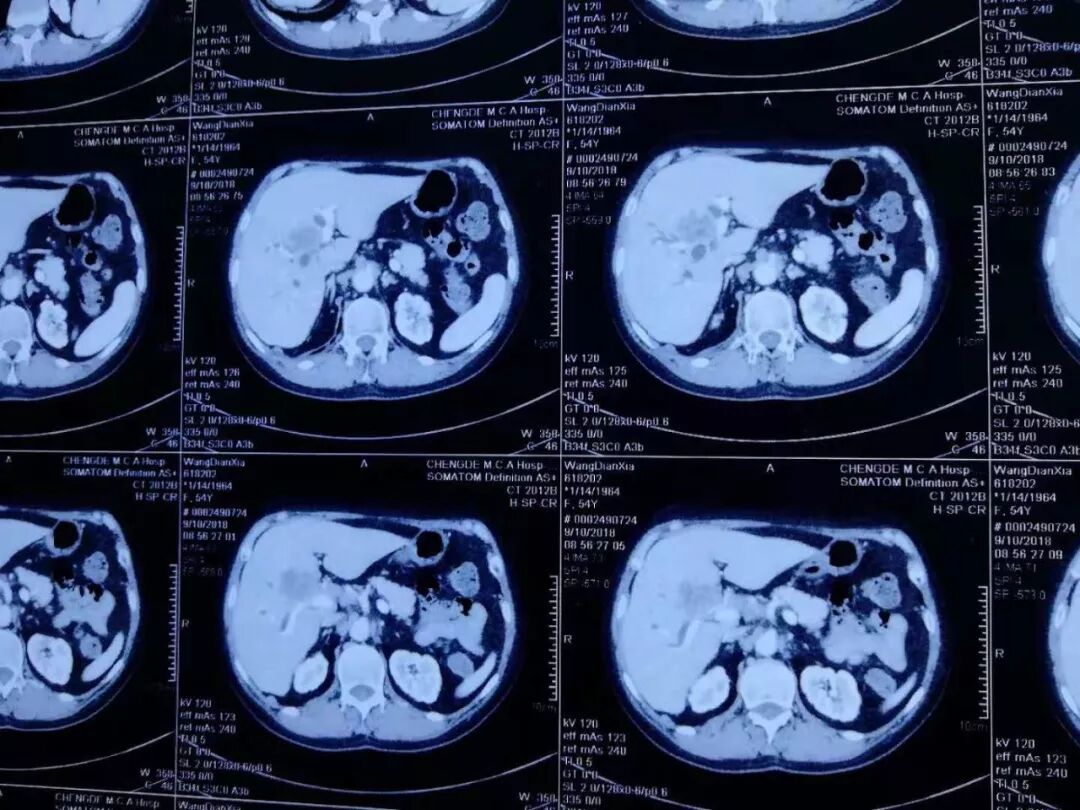

患者王某女性,54岁。患“急性胰腺炎”。后复继发肝内胆管扩张,肝门多发转移淋巴结,肝内多发乏血供小结节,转移瘤待除外。后期护理复杂,甚至可能死在手术台上,患者及家属内心十分恐惧,询问是否有其它解决办法,给予深部热疗,介入,臭氧治疗及靶向药物治疗以后,患者肿瘤明显缩小,一切恢复正常。

2018年10月9号CT复查:

臭氧治疗什么病三氧自体血疗法开启“慢性病、肿瘤”治疗新篇章_https://www.jmylbn.com_新闻资讯_第13张